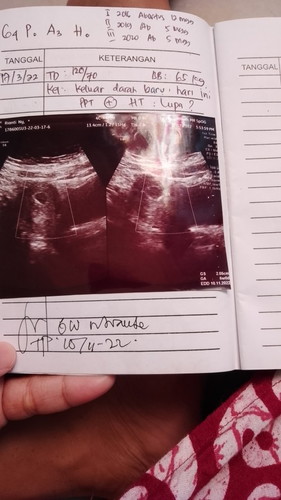

Apakah seperti ini udah ada janin?

Assalamualaikum.. bunda bunda yang baik hati. Mohon infonya donk. Kalau seperti foto USG itu.. apa emang sudah ada janinnya?? Tadi saya periksa kedokter.. kata dokter sudah ada janin. Tapi saya liat dilayar cuma ada warna merah merah gitu.. kata dokternya ini yg warna merah merah janin ya Bu. Trus pas mau denger detak jantung. Pas dicek cuma terdengar sekali aja seperti bunyi deg.. setiap dicari gitu juga sekali aja bunyinya. Kata dokter kantung kehamilan saya lumayan lebar.. trus janin kecil. Sebenarnya janinnya yg mana bund.. terimakasih.. sehat selalu untuk bunda bunda.. #bantusharing